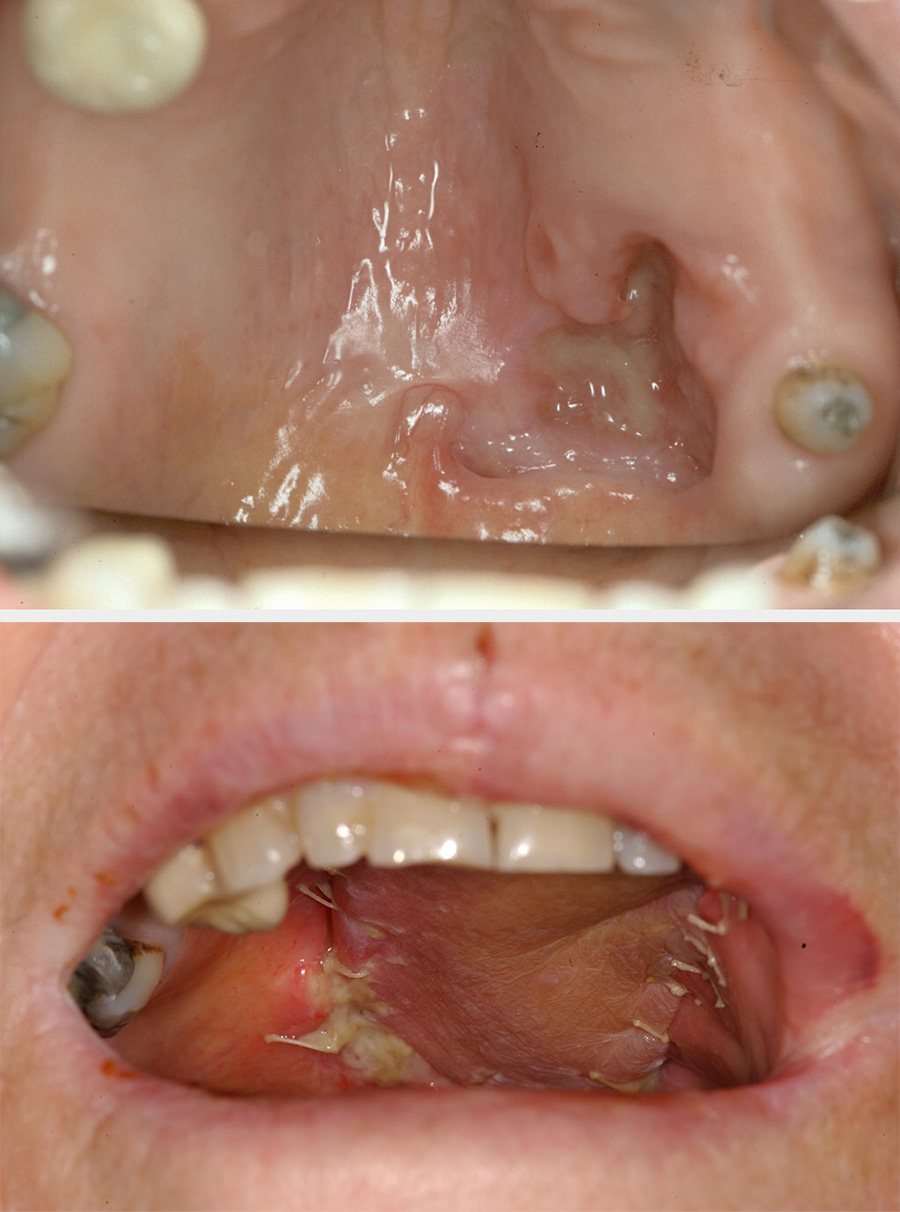

Ventral (underside) tongue and floor of the mouth

The main aim in reconstructing these defects is to allow maximal movements of the residual tongue so that the best possible speech, eating and swallowing can be achieved. Small lesions can be excised with a laser and left to heal or can be excised and repaired with a skin graft, or the wound sometimes can be primarily closed with sutures (longitudinal better than transverse to reduce tethering). Larger defects can be repaired with a local flap (for example, a nasolabial flap or a radial forearm free flap).

Where the majority of the tongue has been removed, there will be little or no residual function. This defect is best reconstructed with bulk (for example, a pedicled pectoralis major flap) or large free flaps such as a latissimus dorsi flap (see Figure 5), or a rectus abdominis flap.